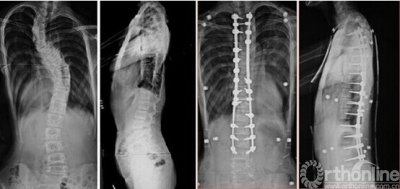

14岁男性患儿,休门氏病后凸畸形(重度,体重260斤),行顶椎多节段Ponte截骨术,术前术后X线片对比